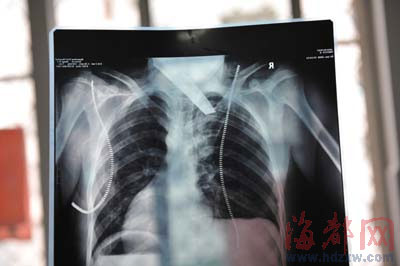

前晚,在第一醫(yī)院急救室,經過4個多小時的搶救,醫(yī)生將匕首從小勇身上取出,發(fā)現(xiàn)這把匕首的刀尖扎斷了1厘米。由于小勇肺部被刺中,昨天上午,醫(yī)生再次進行了3個多小時的手術,切除了受傷的部分肺,直到下午,小勇才挺過來!巴α艘灰,現(xiàn)在總算醒了過來!睏钆恳灰箾]睡,守在手術室外7個多小時,生怕兒子再醒不過來。不過,由于傷勢嚴重,小勇目前戴著氧氣呼吸,仍未脫險。